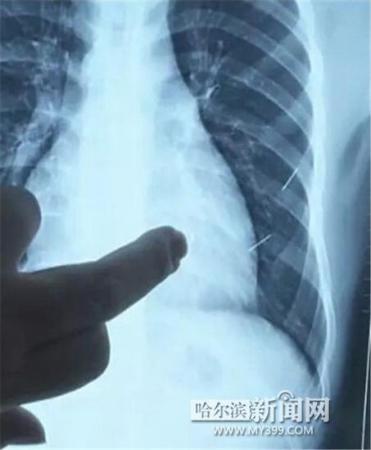

醫(yī)生指出X光片上的針狀物

昨日上午,記者在哈醫(yī)大二院第八住院部心外三病房找到了躺在病床上痛苦不堪的董立仁,家屬正在他身旁不斷安慰著他。見記者前來,董立仁母親李百燕拿出一張X光片,上面可以清晰地看到胸腔內(nèi)一共有4根針狀物,其中一根在心臟部位,兩根在胸腔壁上,還有一根在腹腔壁上。

心外三病房董立仁的主治醫(yī)生告訴記者,董立仁送到醫(yī)院時病情很危險,隨時可能危及生命。“通過檢查發(fā)現(xiàn),他心臟內(nèi)有一個金屬異物,正好在心臟上。心臟每次跳動都與其產(chǎn)生摩擦,導致出血,心包積液懷疑是血液。如果大量出血會凝結(jié)成血塊,血塊包裹住心臟就會影響心臟跳動,隨時都有停跳的危險。心臟上的異物是致命傷,其余胸腔壁和腹腔壁的異物傷害不大。”

昨天16時30分左右取針手術開始。因鋼針隨時會危及患者生命,此次手術定義為大型手術。開胸后,醫(yī)生打開董立仁心包,發(fā)現(xiàn)一枚鋼針已深深扎入心臟,僅露出1厘米長度在外。拔出鋼針后,醫(yī)生發(fā)現(xiàn),這枚針長達5厘米。受鋼針影響,心包出現(xiàn)大量積液,近800毫升。

隨后,在下胸壁位置,第二枚鋼針順利取出。在尋找另兩枚鋼針過程中,普外、胸外多名醫(yī)生也參與手術,為主刀醫(yī)生提供更為穩(wěn)妥的處理建議。根據(jù)X光片顯示位置,醫(yī)生未在患者體內(nèi)找到剩余兩枚鋼針。醫(yī)生懷疑,其中一枚鋼針可能深藏在肋骨骨膜位置,無法尋找,最后決定結(jié)束手術,做進一步觀察,研究下一次手術方案。